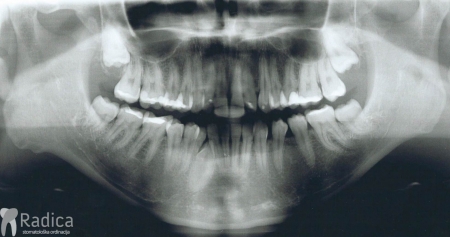

U dolje prikazanim slikama se vidi impaktirani drugi trajni premolar koji je resorbirao dio korijena i krune prvog trajnog molara. Pacijent se javio zbog jakih bolova u području molara koji je bio intaktan te je napravljen ortopantomogram. Molar se morao izvaditi i pacijent je trenutno u terapiji.

U ovom slučaju je 41.godinu starom pacijentu počeo nicati impaktirani desni gornji očnjak pri čemu je ugrozio lateralni sjekutić. Pacijentu je stavljen fiksni aparat te je zub smješten u luk. Kako je pacijent odustao od postave aparata u donjoj čeljusti na kraju nije dobivena zadovoljavajuća okluzija na što je upozoren.

U ovom slućaju 28 godina star pacijent je zatražio ortodontsku terapiju. Na pregledu je uočen perzistentni donji desni mliječni očnjak a ortopan je potvrdio postojanje impaktiranog trajnog nasljednika. Tijekom terapije je uočeno oštećenje korijena desnog lateralnog sjekutića koji je izvađen a na njegovo mjesto je postavljne očnjak i preoblikovan ljuskicom.